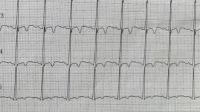

急!求帮忙看看这张心电图!

帮忙看一下心电图,谢谢4/8 分步阅读 看数值 机器会自动打出一些数据, 1、心率:正常为60-100。 100的报“窦性心动过速”。 2、P波:正常时间120ms且呈双峰,报“二尖瓣型P波”(有时···